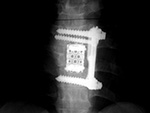

| ILIF: Interlaminar lumbar instrument fusion |

| 85 year-old woman. These images show respectively an AP radiograph of an ILIF at L4-5, an axial CT image of the ILIF, and two coronal reformatted CT images of the ILIF. There is a donar bone plug held in place by the interspinous fixation plate (clamp). |